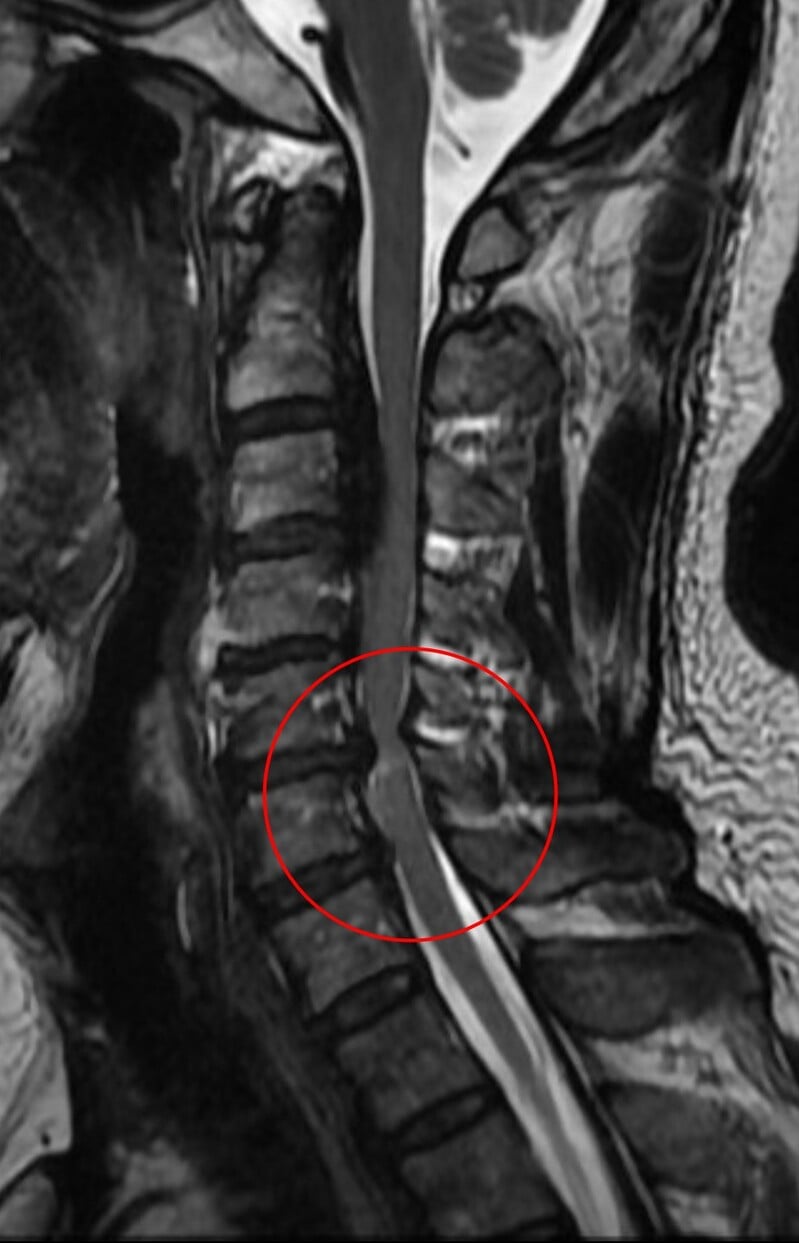

黃先生的頸椎第二節到第六節都有後縱韌帶骨化,其中第五、六節最為嚴重,脊髓已被壓得非常狹窄,核磁共振更可見明顯脊髓空洞,洪祥益主任說,這代表神經已受損,必須盡快手術,若再拖延,一旦跌倒、車禍或頸部突然甩動,都可能造成急性脊髓傷害,增加癱瘓風險。

相較一般骨刺可透過磨除方式處理,後縱韌帶骨化因質地硬且常與硬脊膜緊密沾黏,手術難度與風險顯著提高。洪祥益說明,手術過程需在顯微鏡下精細操作,避免損傷脊髓或造成腦脊髓液滲漏,此外,醫療團隊採取分階段治療策略,第一階段先由前側進行微創手術,直接移除壓迫神經的骨化組織,使脊髓獲得充分減壓;後續再規劃第二階段由後側進行椎板整形術,擴大椎管空間,以降低未來再度壓迫的風險。